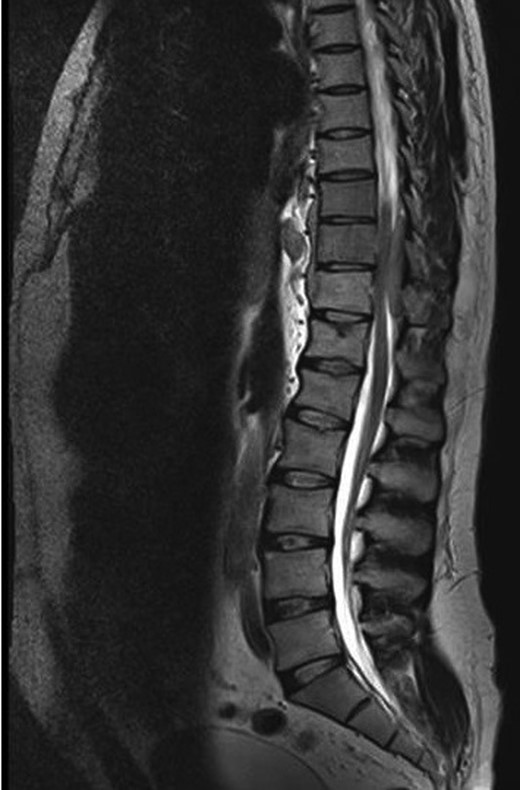

A 30-year-old male patient was admitted to our clinic with back pain. Pain was provoked by movements. The severity of pain was associated with the inability to perform the activities of daily living. The patient did not have any lymphoma-related B-type symptoms, including body weight loss, fever and sweat at night. He did not have a past and family history. There was no neurological deficit. Routine laboratory test results were normal. A magnetic resonance imaging (MRI) scan of the thoracic spine demonstrated an epidural tumor at the T9–11 level (Figs 1–3). The patient underwent spinal cord decompression via total laminectomy of T9–11 levels. Subtotal resection of the tumor was performed. Histological examination revealed the polymorphous cellular infiltration by histiocytes, large mononuclear cells and lacunar Reed–Sternberg cells with folded multi-lobed nuclei and small nucleoli (Fig. 4). Immunohistochemical staining was positive for CD15 and CD30 and negative for CD3, CD20, CD79a or CD45Ro. These features were most frequently observed in the mixed cellularity type of Hodgkin's lymphoma. Histological examination of the vertrebral body revealed no abnormality. The results of all other examinations (F-18 fluorodeoxyglucose positron emission tomography (F-18 FDG PET/CT), bone marrow biopsy and computed tomography (CT) of the chest, abdomen and pelvis) were negative for an occult disease. The patient was referred to the hematology department to undergo staged treatment. Six courses of chemotheraphy containing ABVD regimen (adriamycin, bleomycin, vinblastine and dacarbazine) were given to the patient. Postoperative MRI scan did not reveal any evidence of Hodgkin's disease (Fig. 5), F-18 FDG PET/CT, CT of the chest, abdomen and pelvis were obtained in 24 months and did not reveal any evidence of Hodgkin's disease.

Moridaira et al. [4] reported a case of Hodgkin's disease at T8–10 epidural space. Rao et al. [6] published a case with primary spinal epidural Hodgkin's lymphoma. Our case is apparently the seventh case to be diagnosed with Hodgkin's disease who presented with spinal cord compression due to epidural space without lymphoma elsewhere. The abnormal MRI marrow signal of the T9 and T10 vertebral bodies can be seen in Fig. 5. Maybe the tumor in fact originated within the abnormal T9 or T10 bone marrow and spread to the epidural space via the epidural venous plexus. But histological examination of the vertebral body revealed no abnormality.

Surgery is the first therapeutic approach in malignancies compressing the spinal cord. Because Hodgkin's lymphoma is a very chemosensitive and radiosensitive tumor, the indications for surgery were reduced and limited to laminectomy or even biopsy only, leaving the major role to chemotheraphy and radiotheraphy. The combination of chemotheraphy and involved-field radiotheraphy is the most common treatment strategy; two to four cycles of ABVD are considered as the international gold standard for early-stage Hodgkin's lymphoma in combination with 20–30 Gy of involved-field radiotheraphy [7, 8]. We chose the first therapeutic approach for this patient who underwent gross total resection of the tumor, because the tumor type was unknown at the time of initial presentation. Also, there was severe thoracal spinal cord compression on MRI of our case. Then, the patient was given six courses of chemotheraphy through ABVD regimen.